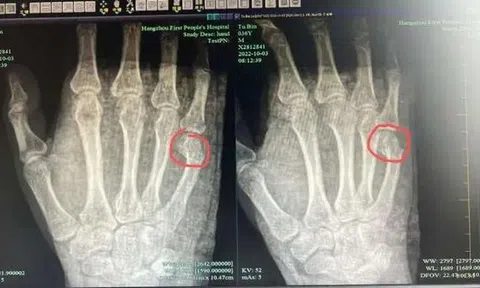

Bố bị gãy xương tay vì làm hành động này trong lúc dạy con học

Hành động trong cơn nóng giận khiến người bố bị đau và sưng tấy lòng bàn tay phải, cần nhập viện để làm tiểu phẫu.